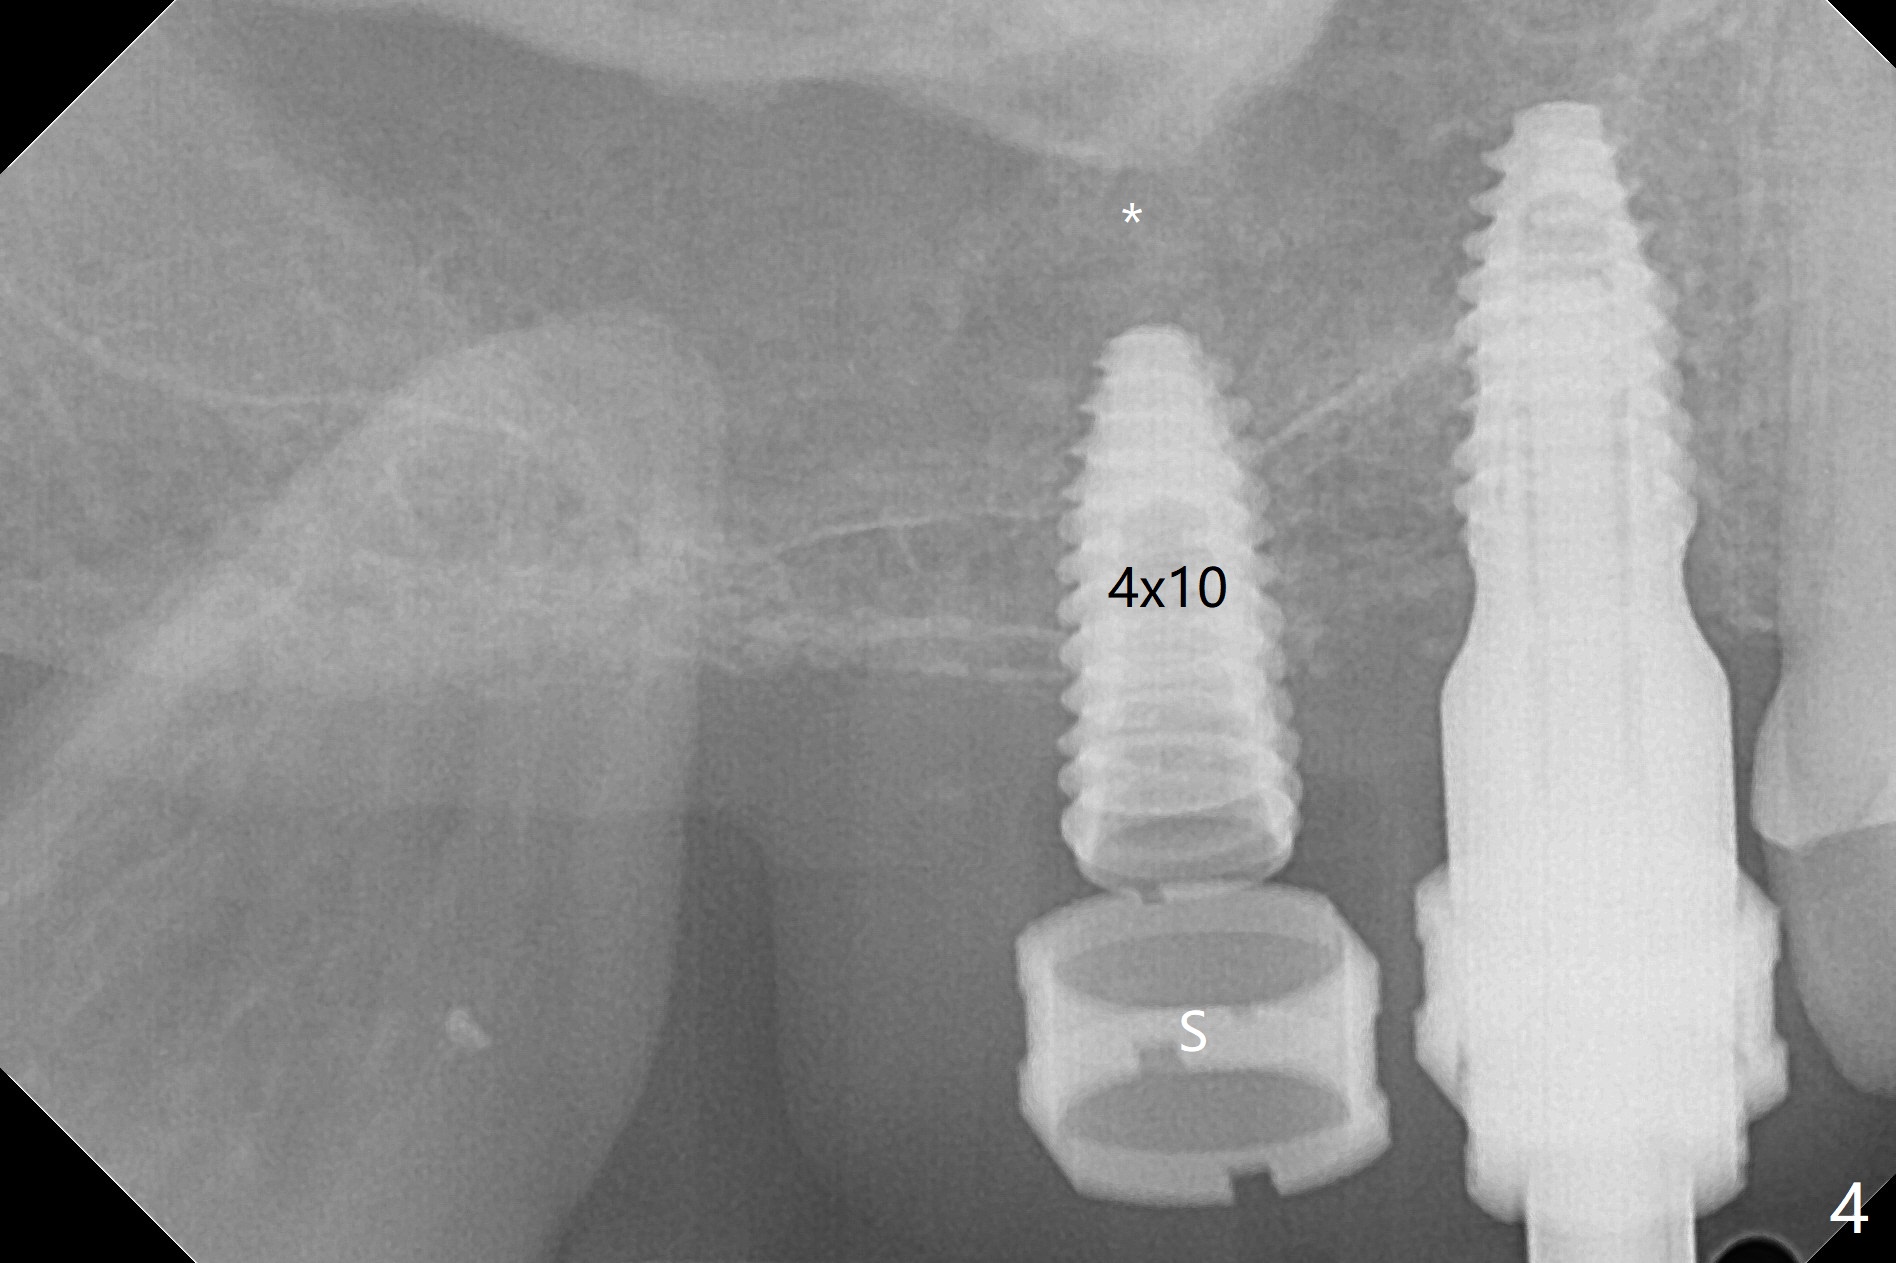

Osteotomy at #3 is performed last (Fig.1,2); as planned, a 4 mm cortical tap is used with guide for sinus lift. Unfortunately the sinus membrane is perforated. Implant placement is aborted. Instead Osteogen plug is inserted into the osteotomy, which is fixed in place by acrylic extending from the provisional at #4. Osteotomy for #3 implant will be attempted with control of the depth in 4 months. The patient has allergy to Amoxicillin (rash). When switching to Clindamycin, she develops diarrhea and loses 10 pounds. There is no abnormality at the site of #3 or 4 nearly 3 months postop (Fig.3). The next surgery will be most likely conducted without antibiotic 4 months postop. Try to draw blood for PRF. Take PA for #12 and 13 for possible impression. Remove the 3 temporary crowns, seat the guide across the arch and use no-stop fixture mounts at #4, and possibly 12 and 13. Follow the original drill sequence (check perforation after each drill, Fig.11) and use DIONavi sinus approach kit. Also load an appropriate stop for the round bur for sinus lift before hand. Mixture allograft with Metronidazole and PRF. In fact everything goes on as smoothly as planned. Osteotomy at #3 is underprep (3.5 mm in diameter drill instead of 4.0). The sinus floor appears to remain to be absent; 3.2 mm round bur is used for lift, alternating with water pumping. Following insertion of 3 pieces of PRF membranes and Vanilla Graft (Fig.4 *), a 4x10 mm dummy implant is placed. After additional bone graft (Fig.5 *), a final 4.5x7.3 mm implant is placed ~10 Ncm. The implant is placed deeper ~ 1 mm, followed by a 5.5x3 mm healing abutment (Fig.6). The implants at #12 and 13 seem to have osteointegrated (Fig.7). Impression is taken for #4, 12 and 13 with limited vertical space (Fig.8,9). An implant at #14 is being considered. There is faint bone graft around the apex of the implant 4 months postop (Fig.10). The implant sustains 25-30 Ncm torque when a 5.2x4(3) mm cemented abutment is placed. A permanent crown is cemented nearly 5 months postop (Fig.11). For the best cosmetic and masticating results, the occlusal surface should have certain degree of morphology, such as the buccal cusps (Fig.12 white curved lines). The abutment at #3 is placed and torqued to 30 Ncm before re-cementation of the repaired crown (increased occlusal surface contact). In fact the abutment at #4 is incompletely seated with a gap (Fig.13 <). The composite at #5 is dislodged while #3 crown is being repaired (*). The abutment at #4 is loose >1 year post cementation. The abutment remains incompletely seated (gap and longer apical space (double arrows)) when the abutment/crown complex rotates lingual mesiobuccal (Fig.14 curved arrow). Further proximal reduction and lingual rotation distobuccal leads to complete seating (Fig.15). It appears that incomplete seating at #13 is associated with hex mismatch (Fig.16, large apical space), which will be fixed next visit. One week later, the crown and abutment of #4 are seated together after crown repair (Fig.17). Since the abutment margin is subgingival, the crown is cemented, removed with abutment for residual cement removal and reseated with the abutment with torque at 30 Ncm. After this, the crown and abutment of #13 is reseated after mesiobuccal surface is trimmed (Fig.18), followed by pick up impression. A few days later, the crown/abutment are inserted together smoothly, the former cemented and the complex unscrewed for residual cement removal and last torqued at 30 Ncm without any X-ray confirmation.